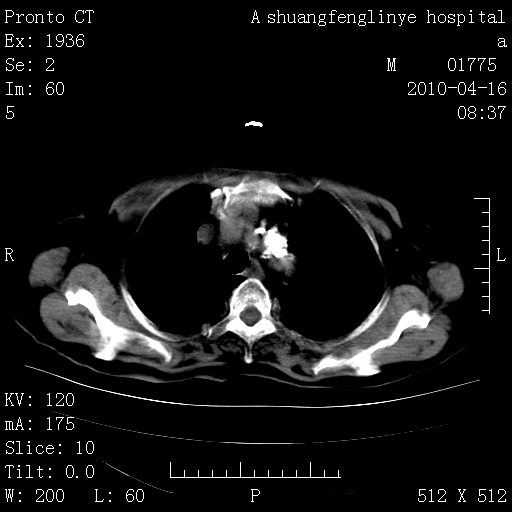

考虑左肺上叶增殖灶、纤维灶。

典型 夹层动脉瘤。 内膜瓣钙化移位

1)左肺上叶结核(纤维、增殖病灶)。2)冠状动脉及主动脉钙化。

1)左肺上叶结核(纤维、增殖病灶)。2)冠状动脉及主动脉钙化。肺动脉高压